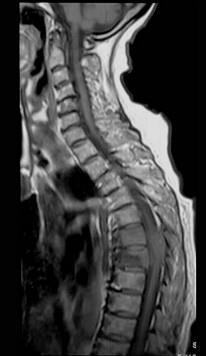

问题 女,72岁,双下肢轻度截瘫3个月余,请结合影像学检查,选出最可能的诊断 ( )

选项 A、脊柱转移瘤 B、强直性脊柱炎 C、脊椎结核 D、化脓性脊柱炎 E、椎体压缩骨折

答案 C